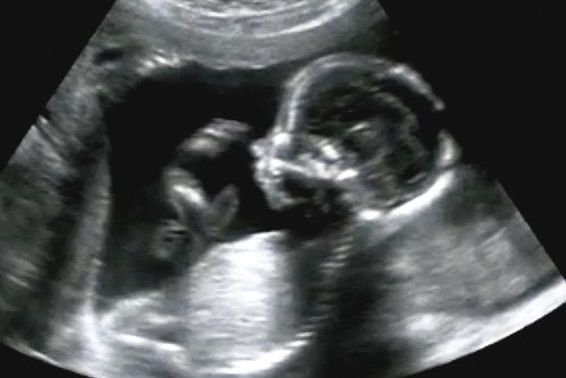

• 胎兒腹壁缺陷Fetal Abdominal Wall Defect

ultrasound_fetus.jpg以下為各種胎兒腹壁缺陷疾病

臍膨出(omphalocele)